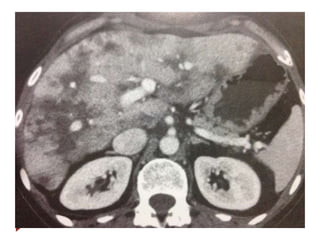

 Hepatocarcinomas

 Se tratados com embolização, radiofrequencia ou crioablação

resposta se não houver realce periférico pelo contraste na TC ou

RM.

Outros critérios modificadoresdo RECIST  Alguns tumores especiais já consideram densidade e padrão de realce.  Mesoteliomas  Medida dificultada pela curvatura da parede torácica.  Medir perpendicular a parede, em 2 locais, cada um em 3 níveis = soma das 6 medidas. Preferir porção superior do tõrax.  GIST  Boa resposta = redução de 10% dimensões e 15% da atenuação na TC.  Progressão = lesões novas, aumento tamanho 20% ou não mudança de densidade.  Hepatocarcinomas  Se tratados com embolização, radiofrequencia ou crioablação resposta se não houver realce periférico pelo contraste na TC ou RM.